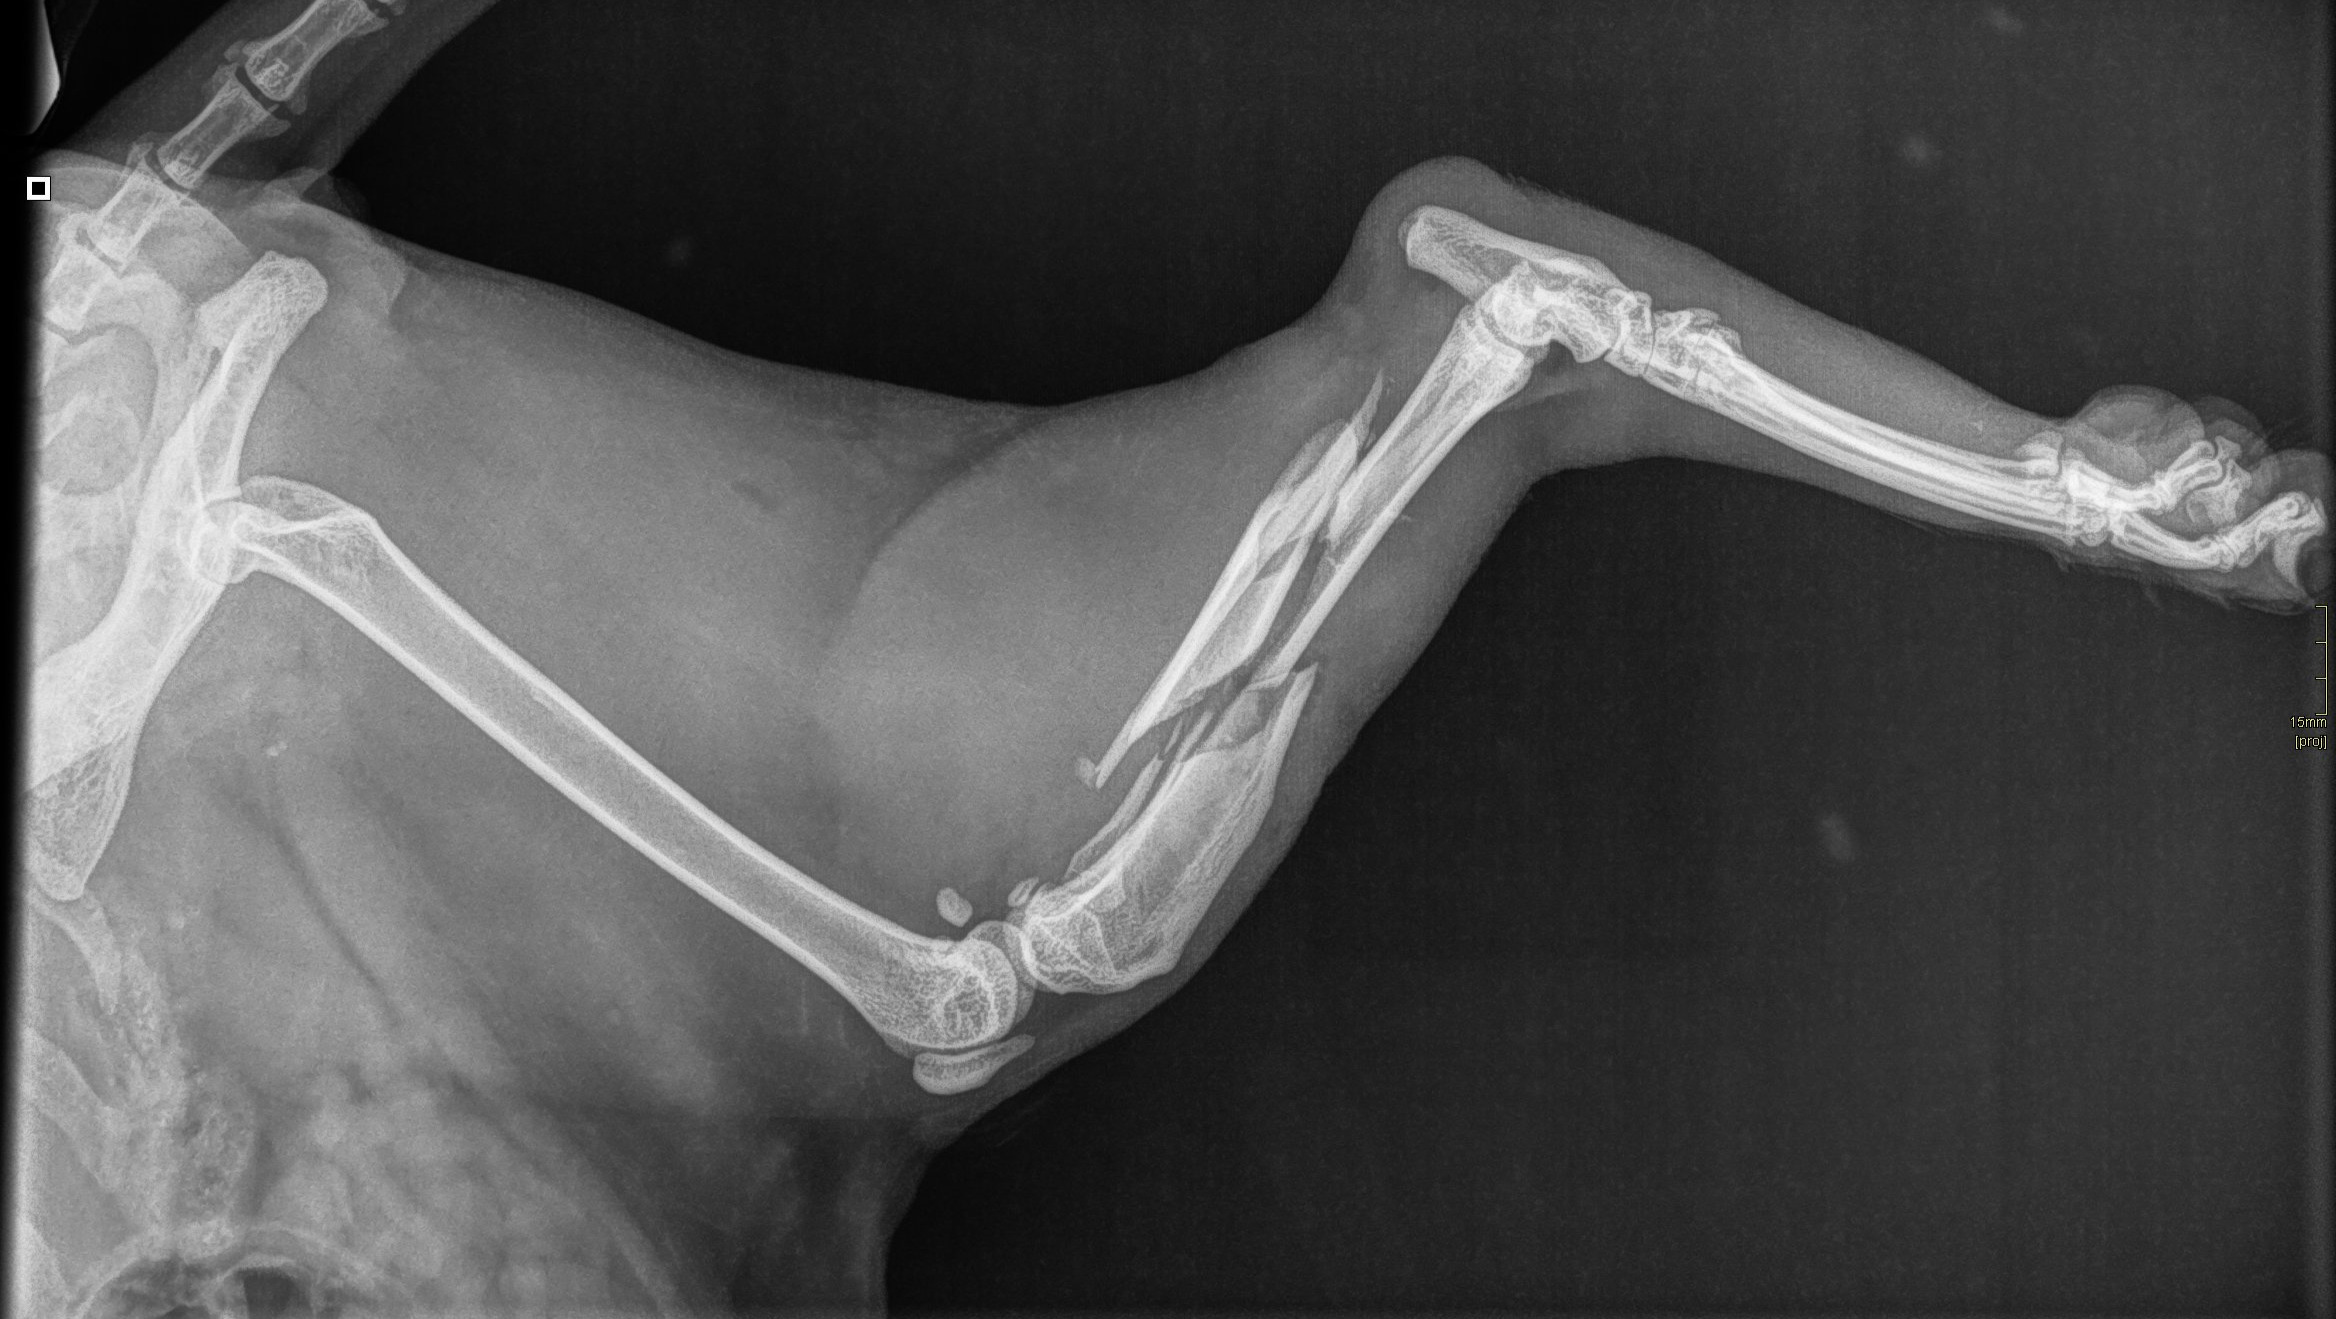

Hij heeft hierbij zijn rechter achterpoot flink gebroken en is zijn linker achterpoot uit de kom gegaan met een barst in zijn gewricht.

Omdat hij beide poten heeft verwond was amputatie van de gebroken poot niet mogelijk omdat hij dan nooit meer goed zou kunnen herstellen op zijn andere poot.

He broke his right hind leg badly and his left hind leg dislocated with a crack in his joint.

Because he had injured both legs, amputation of the broken leg was not possible because he would never be able to recover properly on his other leg.

He has now undergone this surgery and now has an external fixation through his bones to allow it to heal.